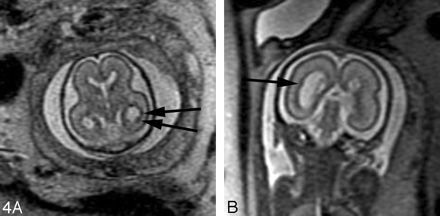

In our experience, fetal MR imaging is especially useful in detecting malformations of cortical development in fetuses with sonographically isolated ventriculomegaly. When interpreting fetal MR images in this clinical setting, the margins of the lateral ventricles should be carefully scrutinized for any areas of nodularity that may represent periventricular nodular heterotopia. Such nodules are isointense to the germinal matrix (Fig 4). Periventricular nodular heterotopia, however, are indistinguishable from the subependymal nodules present in tuberous sclerosis, and other manifestations of tuberous sclerosis, such as transmantle dysplasias, cortical tubers, and cardiac rhabdomyoma, should be sought when ventricular nodularity is identified (Fig 5). Cortical malformations, such as polymicrogyria, can be identified by noting alteration of the normal sulcation pattern for a fetus’ particular gestational age (Fig 6A); they may be identified as too many sulci in a less mature fetus or as too few or abnormally deep or abnormally located sulci in a more mature fetus. The identification of malformations of cortical development in the setting of ventriculomegaly should raise the possibility of a genetic (including metabolic disturbances) or an infectious cause of the ventriculomegaly.

A, 22-week old fetus with several nodular areas of low signal intensity along the margin of the left lateral ventricle (arrows) on axial SS-FSE T2-weighted image. This was confirmed on coronal SS-FSE T2-weighted images (not shown) and is consistent with periventricular nodular heterotopia; and was confirmed at autopsy.

B, 23-week-old fetus with smaller nodular area of low signal intensity along the atrium of the right lateral ventricle (arrow) on coronal SS-FSE T2-weighted image. Finding was confirmed on axial image (not shown). Findings are also consistent with periventricular nodular heterotopia in this fetus with a family history of periventricular nodular heterotopia.